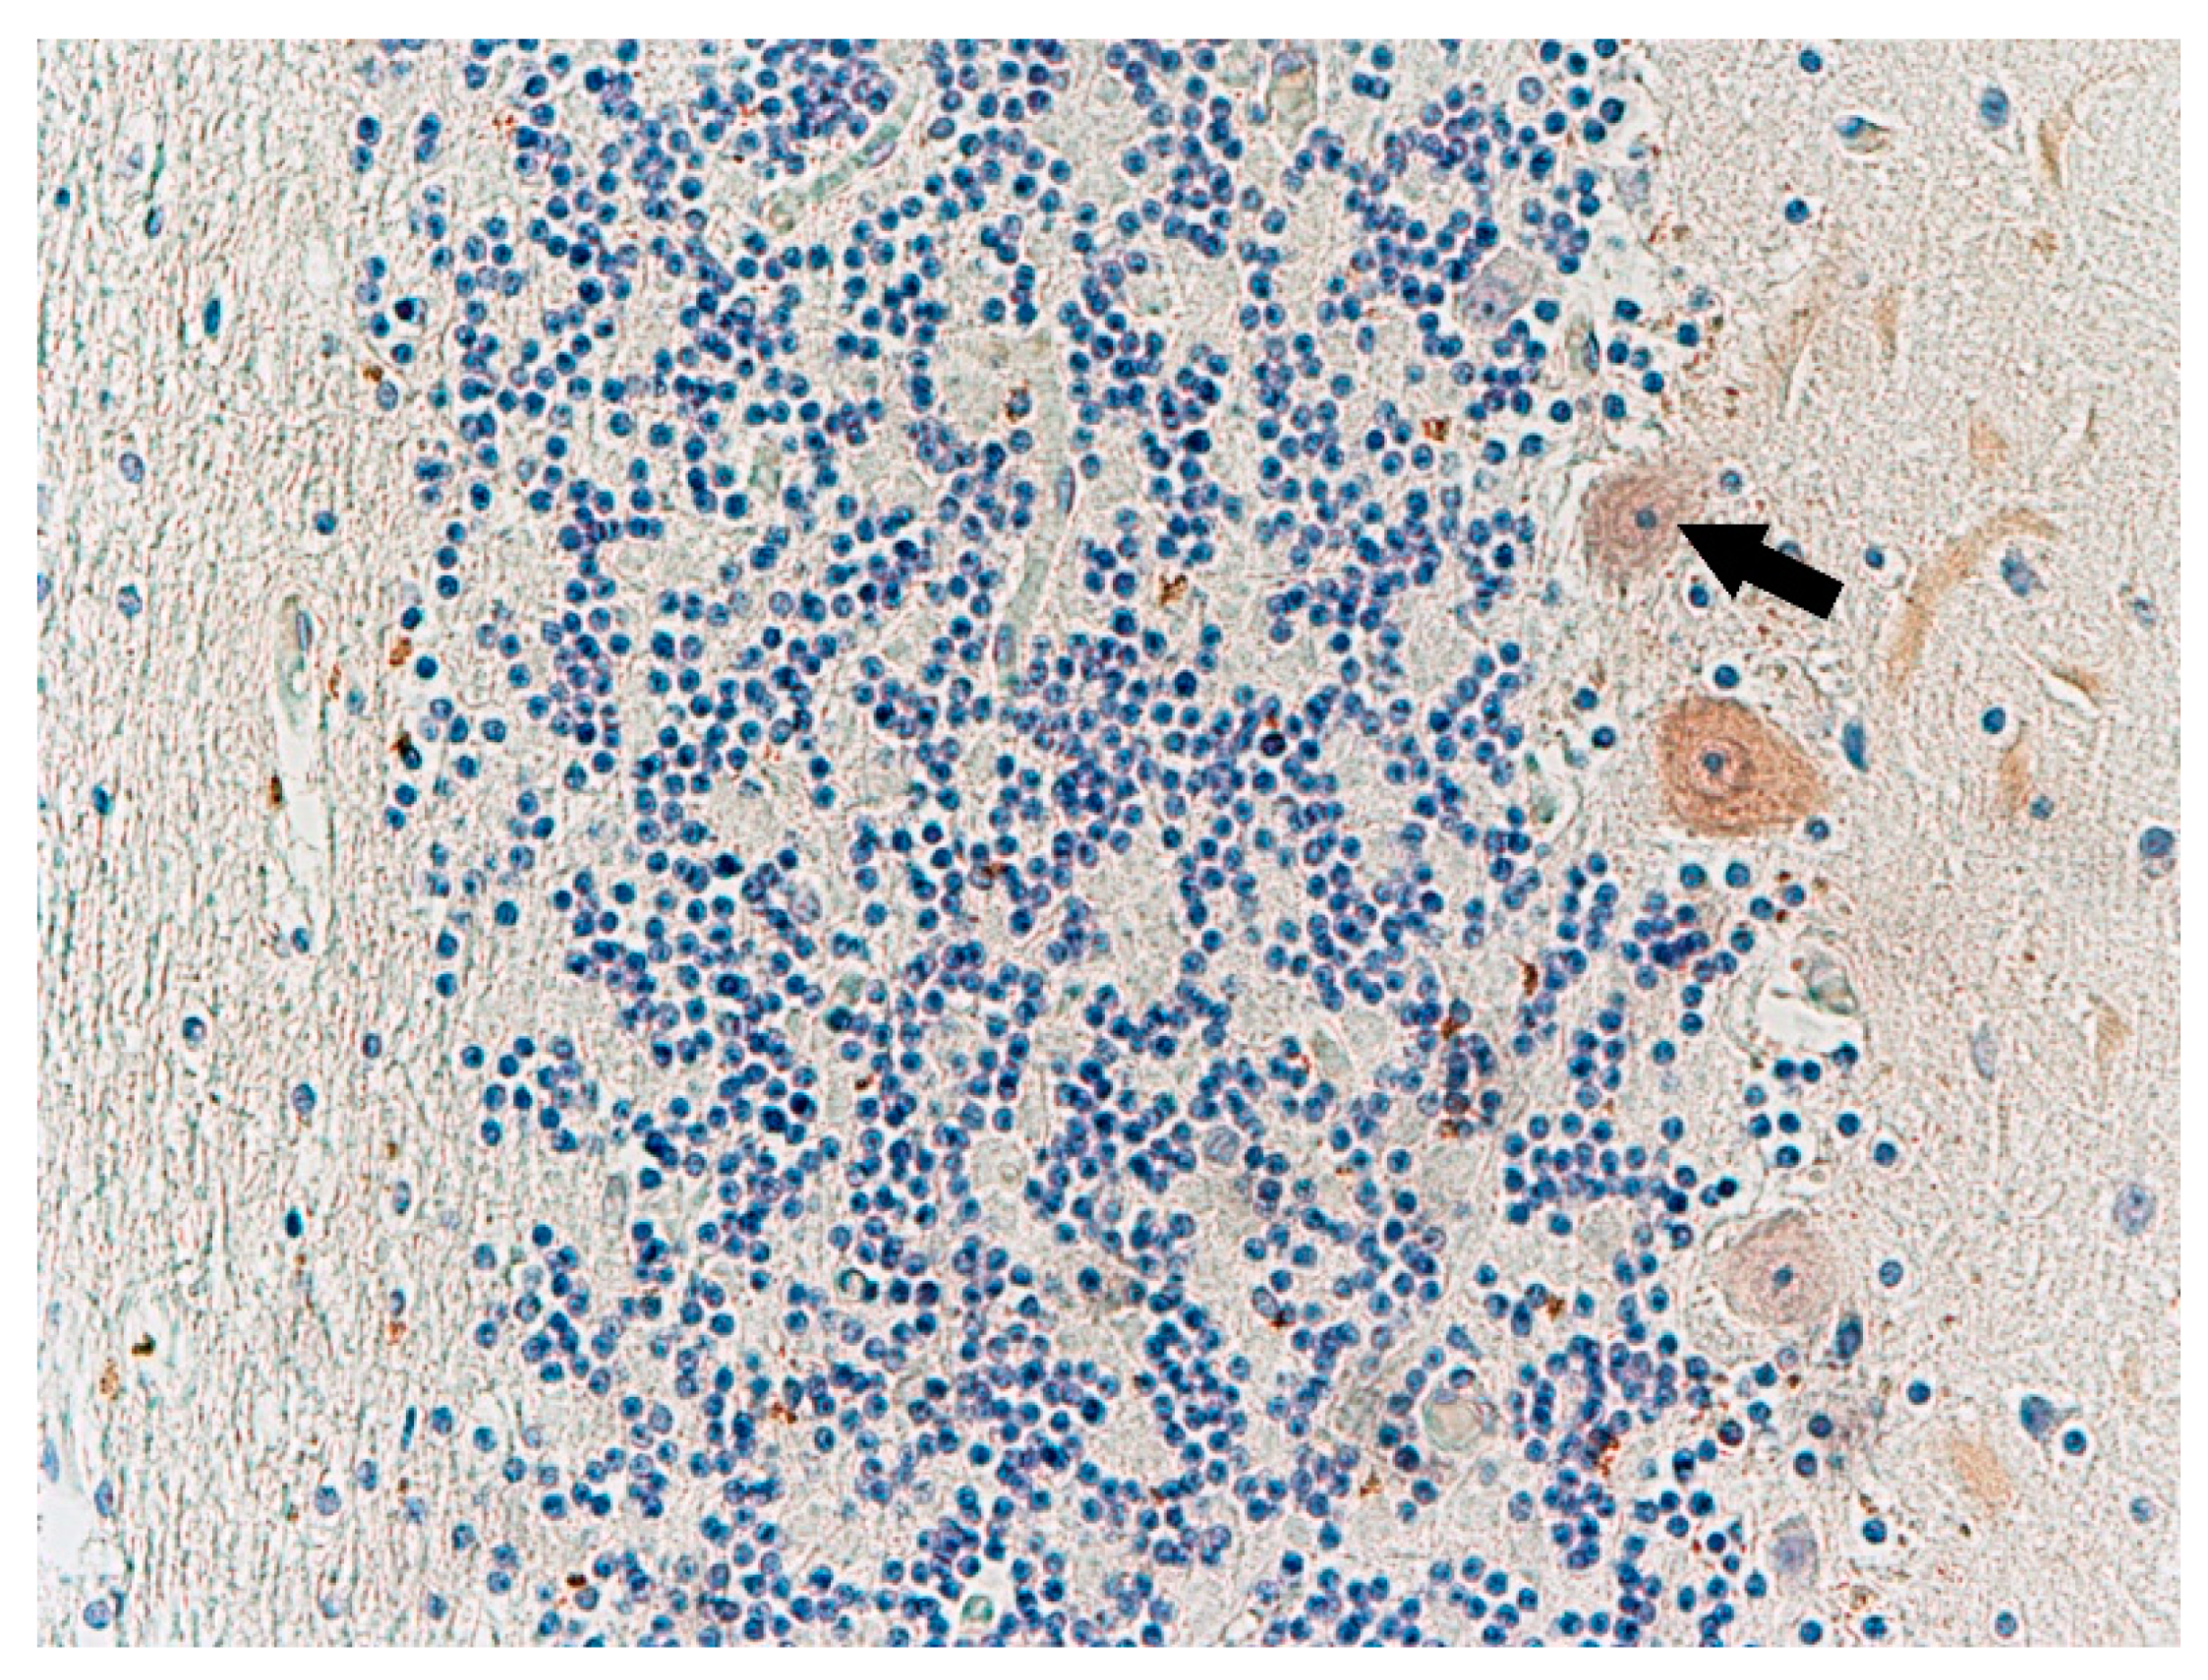

Histochemical Methods